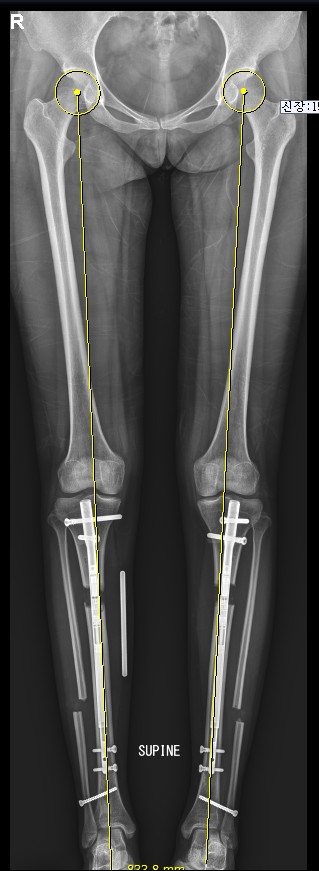

3등은 종아리 속성연장입니다. 종아리 속성연장은 여러 면에서 가장 많이 시행되는 보편적이고도 가장 이변이 없는 안정적인 수술이지만, 핀 통증은 키 연장 후반부에 환자들을 괴롭힙니다. 이때가 재활치료가 가장 필요한 시기지만, 재활 치료를 못하게 괴롭히는 방해자도 이 핀 통증입니다. 재활치료를 줄이면 연장은 더 할 수 있지만, 정확한 정렬 사진 측정이 불가능해지므로 재활이 부족한 종아리 속성연장 환자들은 정확한 정렬사진을 찍기 불가능하고, 2차 수술인 외고정 제거수술을 하고 난후 교정수술을 해야 하는 경우가 종종 있습니다. 고연장은 하고 싶고, 재활은 못하겠다는 상황이 많은 재활을 힘들어 하는 종아리 속성연장 환자에게서 나타나는 현상입니다. 외고정을 제거 후에 교정을 다시 하는 수술실 교정은 비교적 간단하지만, 가능한 2차 수술 외고정 제거 수술 전에 재활을 충분히 한 후 정렬교정을 마치는 것이 유리합니다.